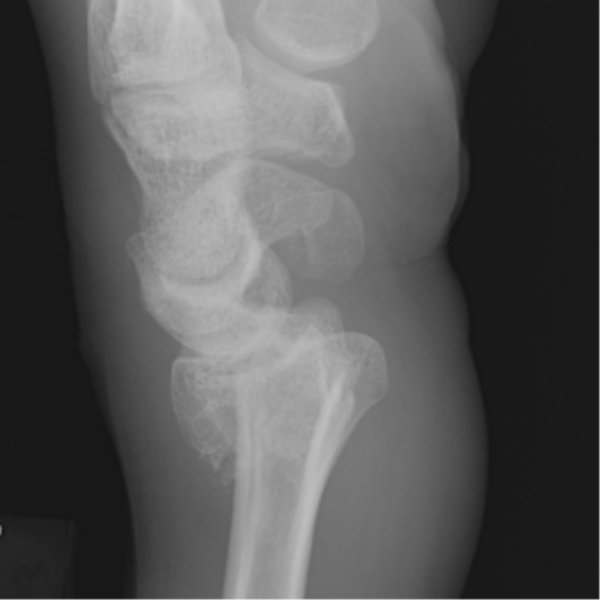

Return to Colles Fracture